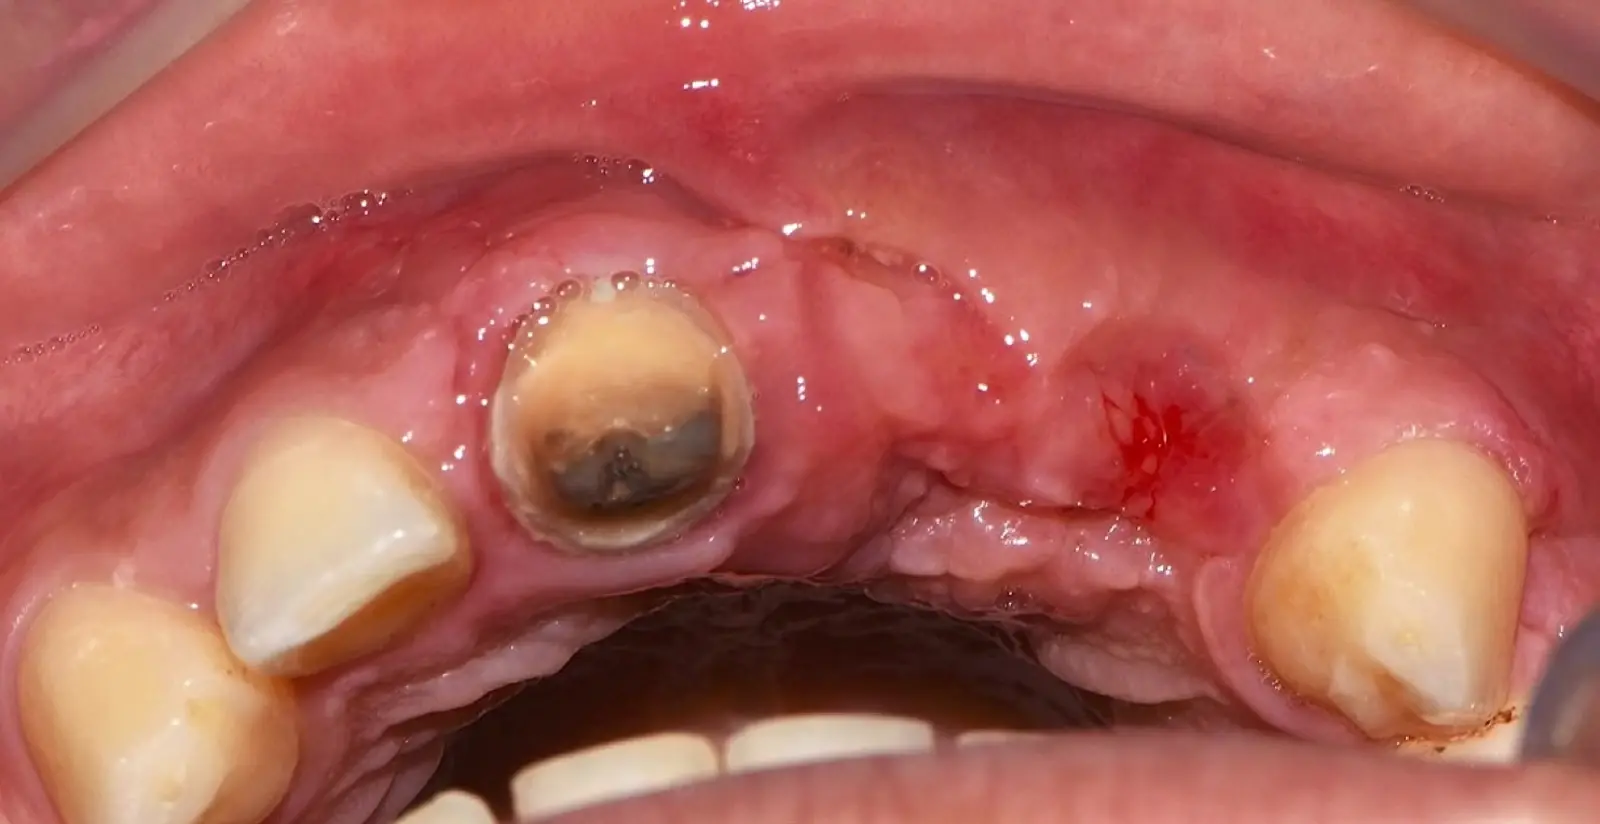

En las imágenes superiores se aprecia una reconstrucción de reborde con injertos en bloque previo a la planificación de implantes; en las imágenes inferiores, se observa la deficiencia vertical del reborde óseo y el tratamiento realizado con el piezoeléctrico.

Paciente de sexo femenino de 36 años de edad, llega a la consulta por presentar una restauración protésica inadecuada. En el examen clínico se observa una restauración protésica provisional acrílica sobre las piezas 1.1 y 2.2. Adicionalmente, se aprecia recesión gingival a nivel de la pieza 2.2 y deficiencia horizontal severa de reborde a nivel de la zona edéntula correspondiente a la pieza 2.1. En la evaluación tomográfica se observa ausencia total de tabla ósea vestibular en la pieza 2.2, y se corrobora el déficit en la zona edéntula de la pieza 2.1, para lo cual se indica una reconstrucción de estructuras óseas con hueso en bloque de origen bovino y posteriormente la colocación de implantes dentales.

Figura 34. Vista frontal donde se observa deficiencia vertical del reborde óseo a nivel de las piezas 2.1, 2.2.